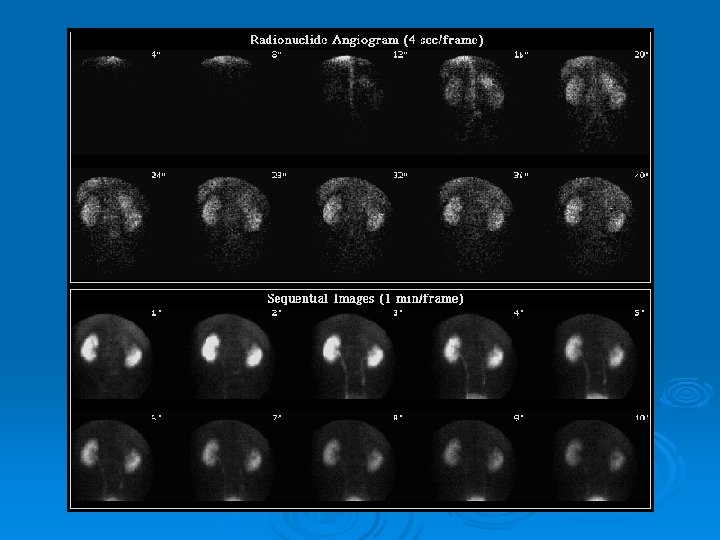

Renal transplant scan; Ø Essential part of transplant department. Ø Best tracer: 99 m. Tc-MAG 3. Ø Perfusion and function analysis Ø Useful in DDx of transplant complications: ATN, Rejection, Cyclosporine toxicity, Obstructive disease, Urinoma, Lymphocele, …

Renal transplant scan: TRS Ø Two Aspects: l l Ø Perfusion phase Function Phase Choice; Tc 99 m-MAG 3 l l Good quality perfusion images High extraction rate • Excellent images l Evaluation of collecting system, ureter and bladder

TRS: Perfusion Ø Images Ø Curves

TRS: Functional Phase Ø Images Ø Curves l l l Uptake: Tc 99 m-MAG 3: Max: before : 5 min Parenchymal transit Excretion of the tracer